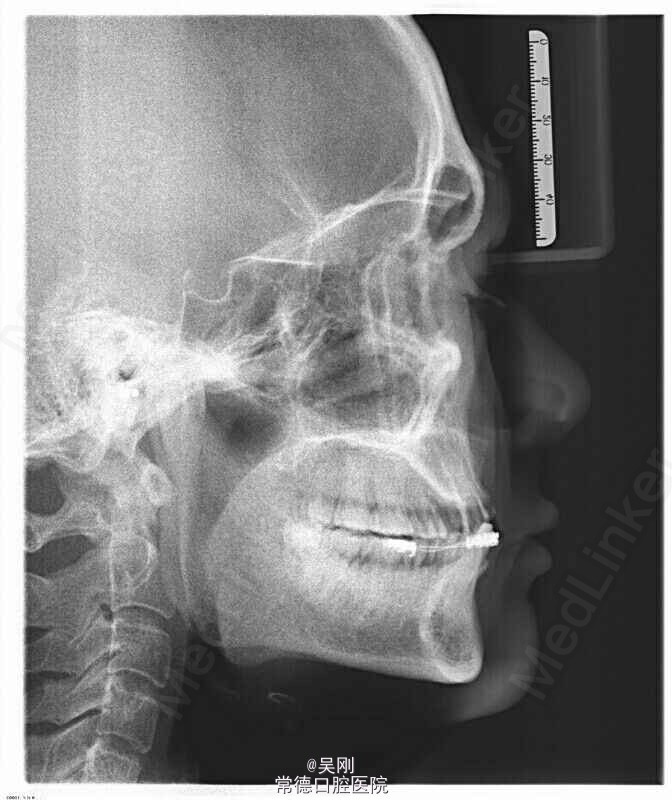

11、12、21缺失,牙槽骨(唇侧更明显)吸收严重成月牙状。 22残根断面距龈上约1.5mm,13牙髓坏死。 深覆 牙合 。 下前牙之间有间隙。 缺牙区距离太长,超过实际距离。 X线显示下前牙与上颌缺牙区牙槽嵴角度成反 牙合 。

上颌牙列缺损。 1.戴 牙合 垫,暂时恢复美观并为粘固下颌托槽开辟间隙。为防止 牙合 垫压低后牙而影响定位咬合关系,牙合 垫在前磨牙处不接触,距离抬高到能粘固托槽就好,尽量缩短佩戴时间。 2.将托槽按同一平面粘固,前牙减径约1mm(加上本身的间隙共产生约2.5mm),直接用圆丝(硬丝)挂一类牵引,使前牙牙轴具有舌向关闭间隙。 3.基牙预备,因缺牙区跨度超过实际长度选择增加14做基牙。 4.完成烤瓷桥。 5.X线显示磨牙还是有点牙低,下前牙明显内收,于上颌牙槽嵴关系改善。 6.因磨牙压低,下前牙舌侧固定保持。磨牙自己建 牙合 。